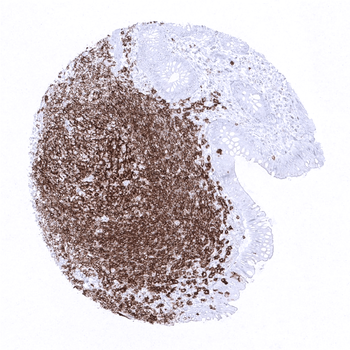

CD20 antibody validated for immunohistochemistry on 76 different Normal Tissues

In the tonsil, many lymphocytes stain positive while the surface epithelium is CD20 negative.

The thymus contains a relatively low fraction of CD20 positive B-lymphocytes.

Strong CD20 staining of a germinal centre in the appendix mucosa while epithelial cells are completely negative.